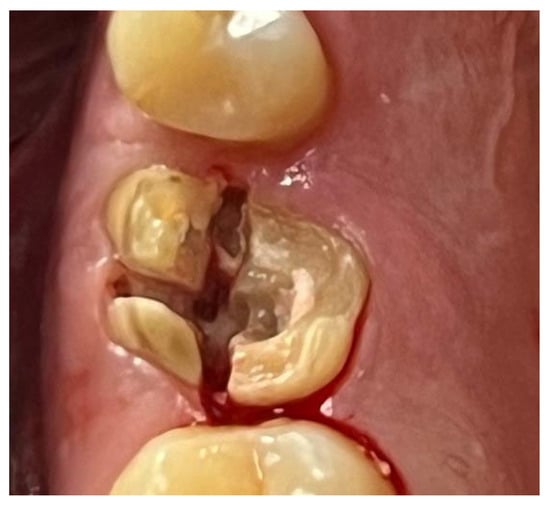

A similar technique was used in a 45-year-old patient with controlled hypertension, treated for the extraction of tooth 1.6 (Figure 11) and subsequent post-extraction implant-prosthetic rehabilitation (Figure 12). The surgical site was treated with bone graft material (Bio-Oss®—Geistlich), and a small amount of Glubran II was applied (Figure 13). Once again, Glubran II proved to be highly effective in stabilizing the graft material at the surgical site, providing excellent hemostasis and strong mechanical resistance from the film formed after polymerization (Figure 14).

Figure 11. Surgical extraction of 1.6.